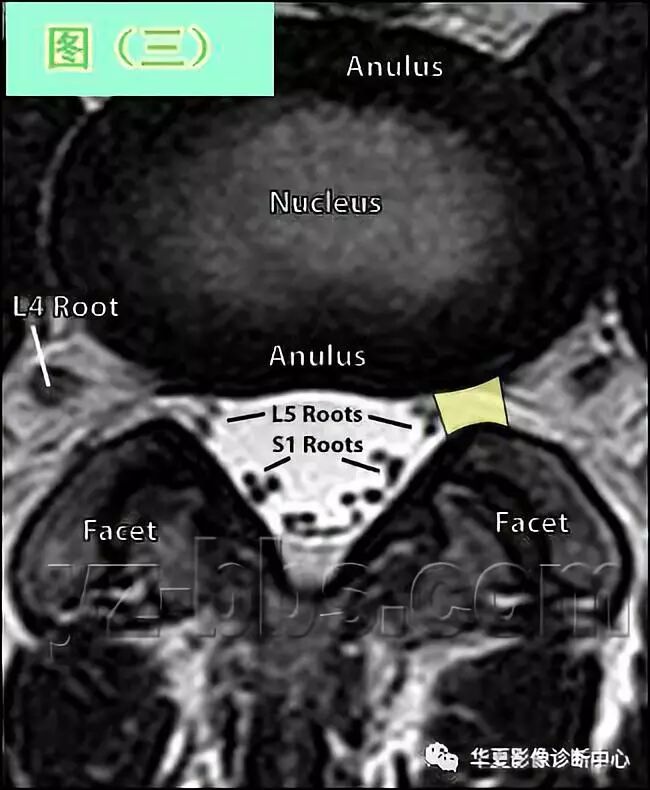

图(三)是另一个健康的45岁男性的L4椎间盘的轴状面观

现在我们可以区分开髓核区及周围的纤椎环区。注意,在此平面将看不到“米老鼠”。另外请注意靠近L5神经根的椎间盘后缘的凹度,这是正常健康椎间盘的象征。L4发出神经根更靠侧方一点。

这就不难理解为什么如果有大的椎间盘突出或椎管狭窄,发出神经根L4及过往神经根L5将同时受压。

在此图中,可清楚地看到悬挂在硬膜囊内的细小的神经根(L5神经根及S1神经根),它们以不完全有绪地状态排列着。

注意,神经孔是很开阔的(浅黄色区),表明没有因邻近椎间关节问题形成在的椎管狭窄。T2加权象对于察看退化性椎间盘病是最好的,因为T2像将富含水份的结构表现为亮白色, 含水少的区域表现为黑色。